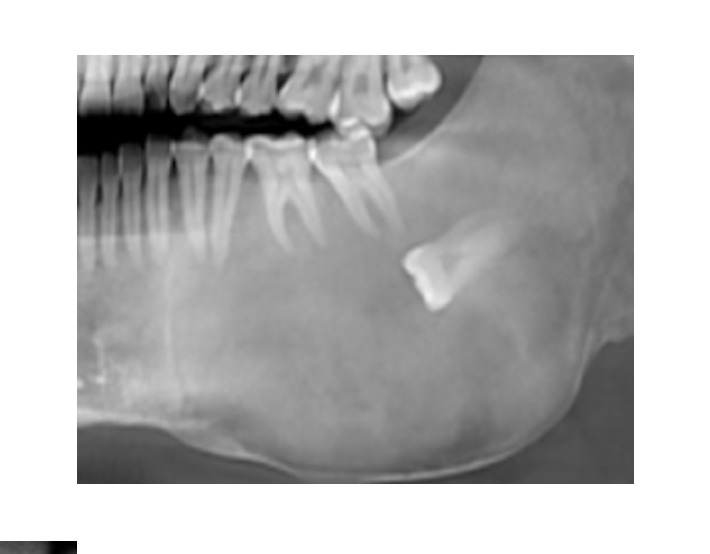

Langerhans Cell Disease

A

Aka Idiopathic Histiocytosis

Rare Cancer

Langerhan cells (Histiocytes):

* normally found in skin as antigen-presenting cells

* Cause damage if buildup in body

Punched out “Ice cream scoop” radiolucencies

* lead to floating teeth